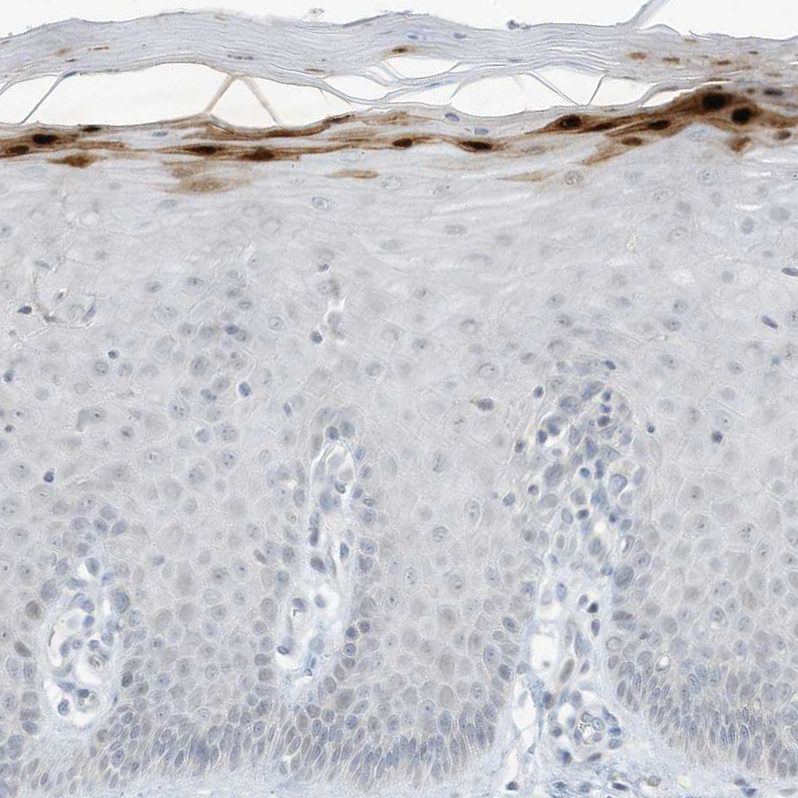

Immunohistochemistry analysis in human skin and liver tissues using HPA034809 antibody. Corresponding ASPRV1 RNA-seq data are presented for the same tissues.